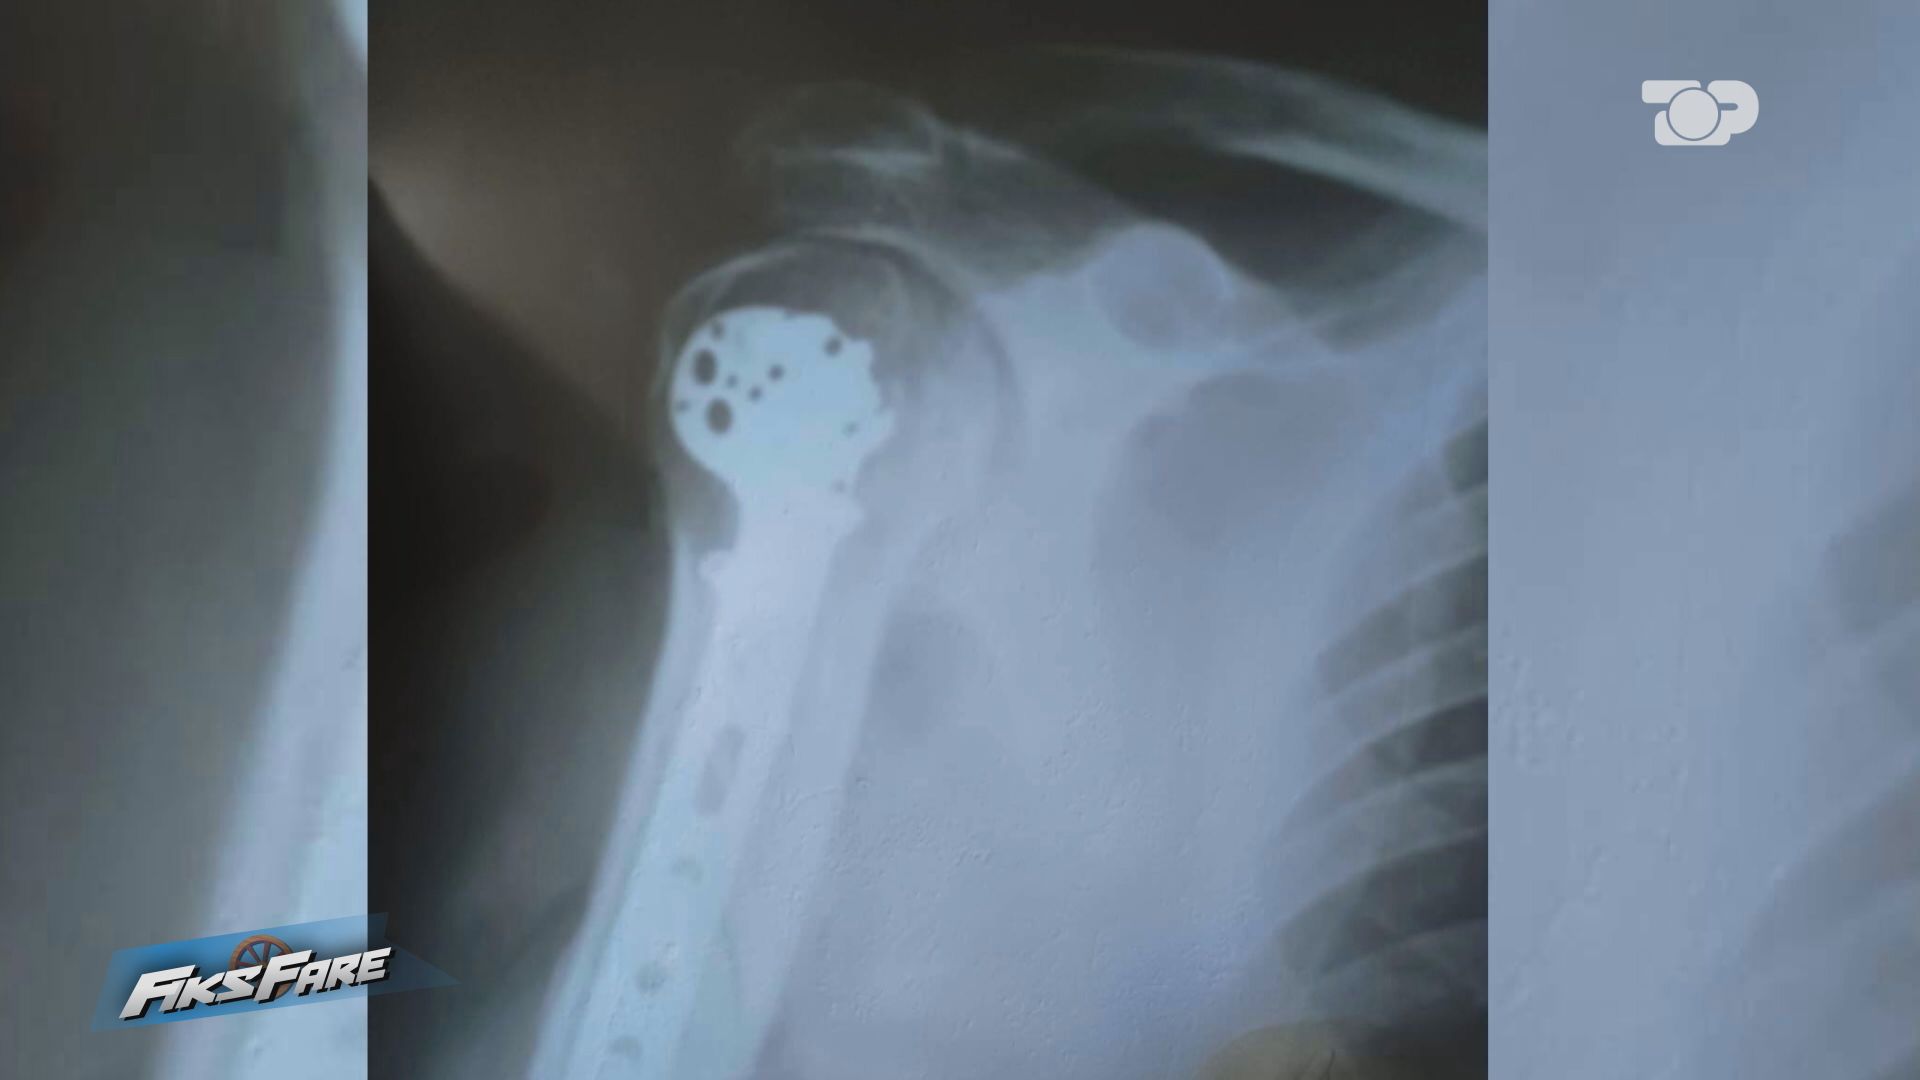

Punonjës të Kadastrës së Dibrës dhunuan barbarisht Meleq Stojkun, i cili kërkoi dokumente nga arkiva. Nga dhuna e ushtruar, qytetari pësoi fraktura të rënda dhe u operua në Spitalin Ushtarak. Ndërkohë, shteti bëri atë që di të bëjë më mirë, e mbylli çështjen.

Prokurori Drini Zeqo u mjaftua vetëm me deklarimet fillestare të denoncuesit gjatë kohës që ishte në Spitalin e Peshkopisë. Ky prokuror nuk urdhëroi asnjë riekspertim të gjendjes të Meleqit, për të parë se çfarë dëmtimesh kishte dhe në çfarë kategorie futen. Në fund, vendosi mos regjistrimin e procedimit penal.

Fiks Fare bisedoi me juristin Gentian Trenova, i cili tha se hetimi i shpejtë për të mos regjistruar procedimin penal, është i nxituar dhe duhet të kishte pritur apo urdhëruar kryerjen e një ekspertimi mjeko-ligjor. Juristi tha se, duke parë fotot dhe gjendjen e qytetarit, kemi të bëjmë me një plagosje. “Për ta përcaktuar nëse është plagosje e lehtë apo e rëndë, duhej të ishte kryer ekspertimi” përfundoi Gentian Trenova.